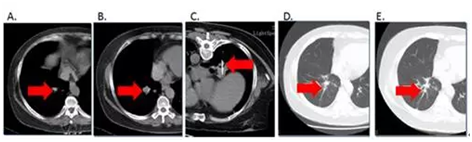

图4:1 例59岁女性晚期非小细胞肺癌患者(EGFR突变)伴肺内转移,口服TKI药物治疗后15月,右下肺肿瘤(图B)如箭头所示较前(图A)明显增大,疾病进展;经CT引导下右下肺肿瘤RFA治疗(图C),后随访3个月(图D)、6个月(图E)均示控制良好。